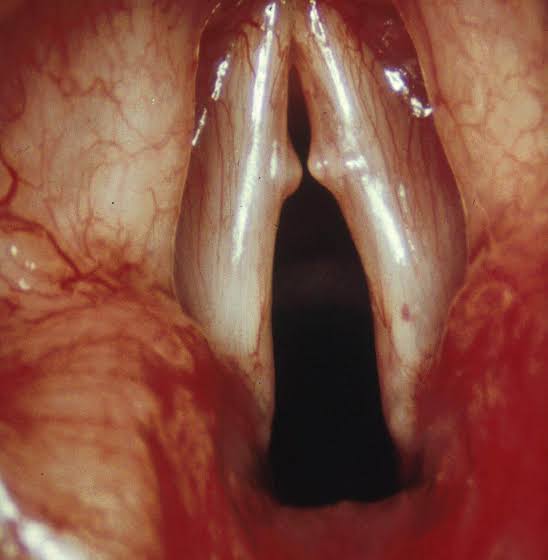

If you sing often, you know what it feels like when your voice starts to sound scratchy, weak, or unreliable. Sometimes that roughness can come from overuse, tension, or too much pressure on your vocal cords. Over time, that strain can lead to small, callus-like bumps known as vocal nodules.

Nodules can affect anyone who uses their voice a lot, including singers, teachers, speakers, and performers. They usually form when certain muscles work too hard while others do not engage enough, causing the edges of the vocal cords to collide too firmly. The good news is that your voice can regain its balance with the right habits and consistent vocal care.